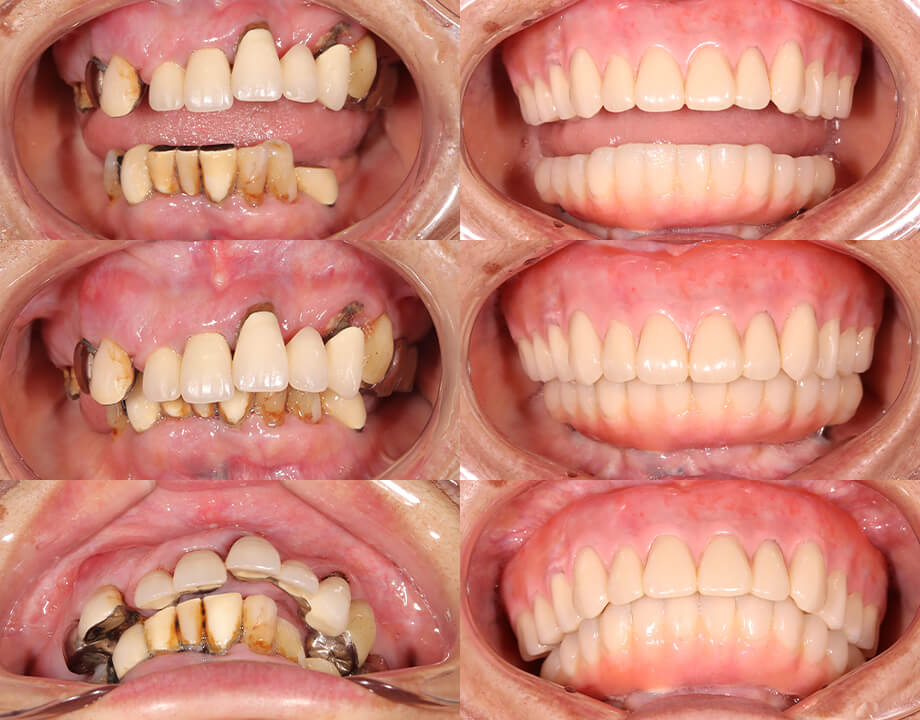

Case 07咬合再構成

アナログワックスアップ

→シュミレーション(ノーベルガイド)

→プロビジョナル(即時荷重)

→最終補綴物(ハイブリッドクラウン)